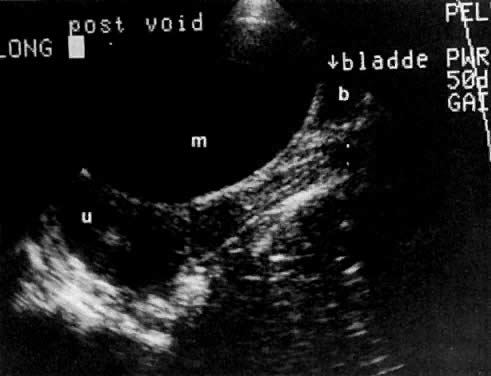

The presence of hydrometras should raise the suspicion of cervical or endometrial carcinoma. It is best demonstrated by ultrasound (see Fig. 6A), but can be seen by both MRI (Fig. 7) and CT (Fig. 8).11,12 This finding, however, is nonspecific because it can also be seen in benign cervical strictures caused by either previous cervical inflammation (Fig. 9) or pelvic irradiation (Fig. 10).

Fig. 9. Sagittal scan of the uterus ( u) shows hydrometras. Cervix ( c) is normal in size. Patient had no known cervical or endometrial cancer.